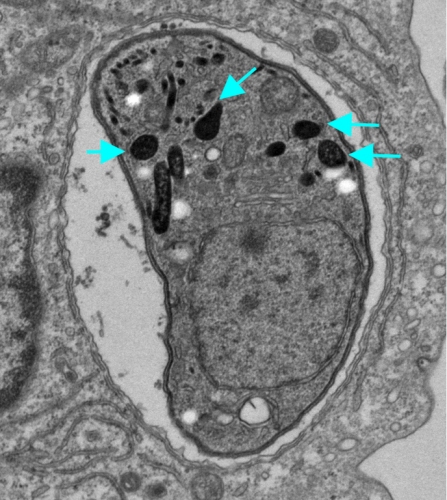

寄生虫トキソプラズマは全世界人口の3分の1が感染しており、健常者の場合は問題ないが、エイズ患者や抗癌剤投与下の患者には致死性の脳症・肺炎・心筋炎などを発症することが知られている。トキソプラズマは自然免疫細胞に潜伏して表面に出てこないため宿主免疫系の監視網を逃れることができるが、その詳細については明らかになっていなかった。

今回の研究では、トキソプラズマが感染細胞中に分泌するGRAタンパク質を哺乳動物細胞内で発現させ宿主転写因子活性化経路の反応を調べたところ、GRA6が免疫制御分子NFAT4を活性化していること、そしてNFAT4を強制的に活性化することで免疫細胞遊走能を有するケモカイン群を誘導し、感染局所に「トロイの木馬」となる好中球を遊走させて全身に感染拡大していくことが分かった。